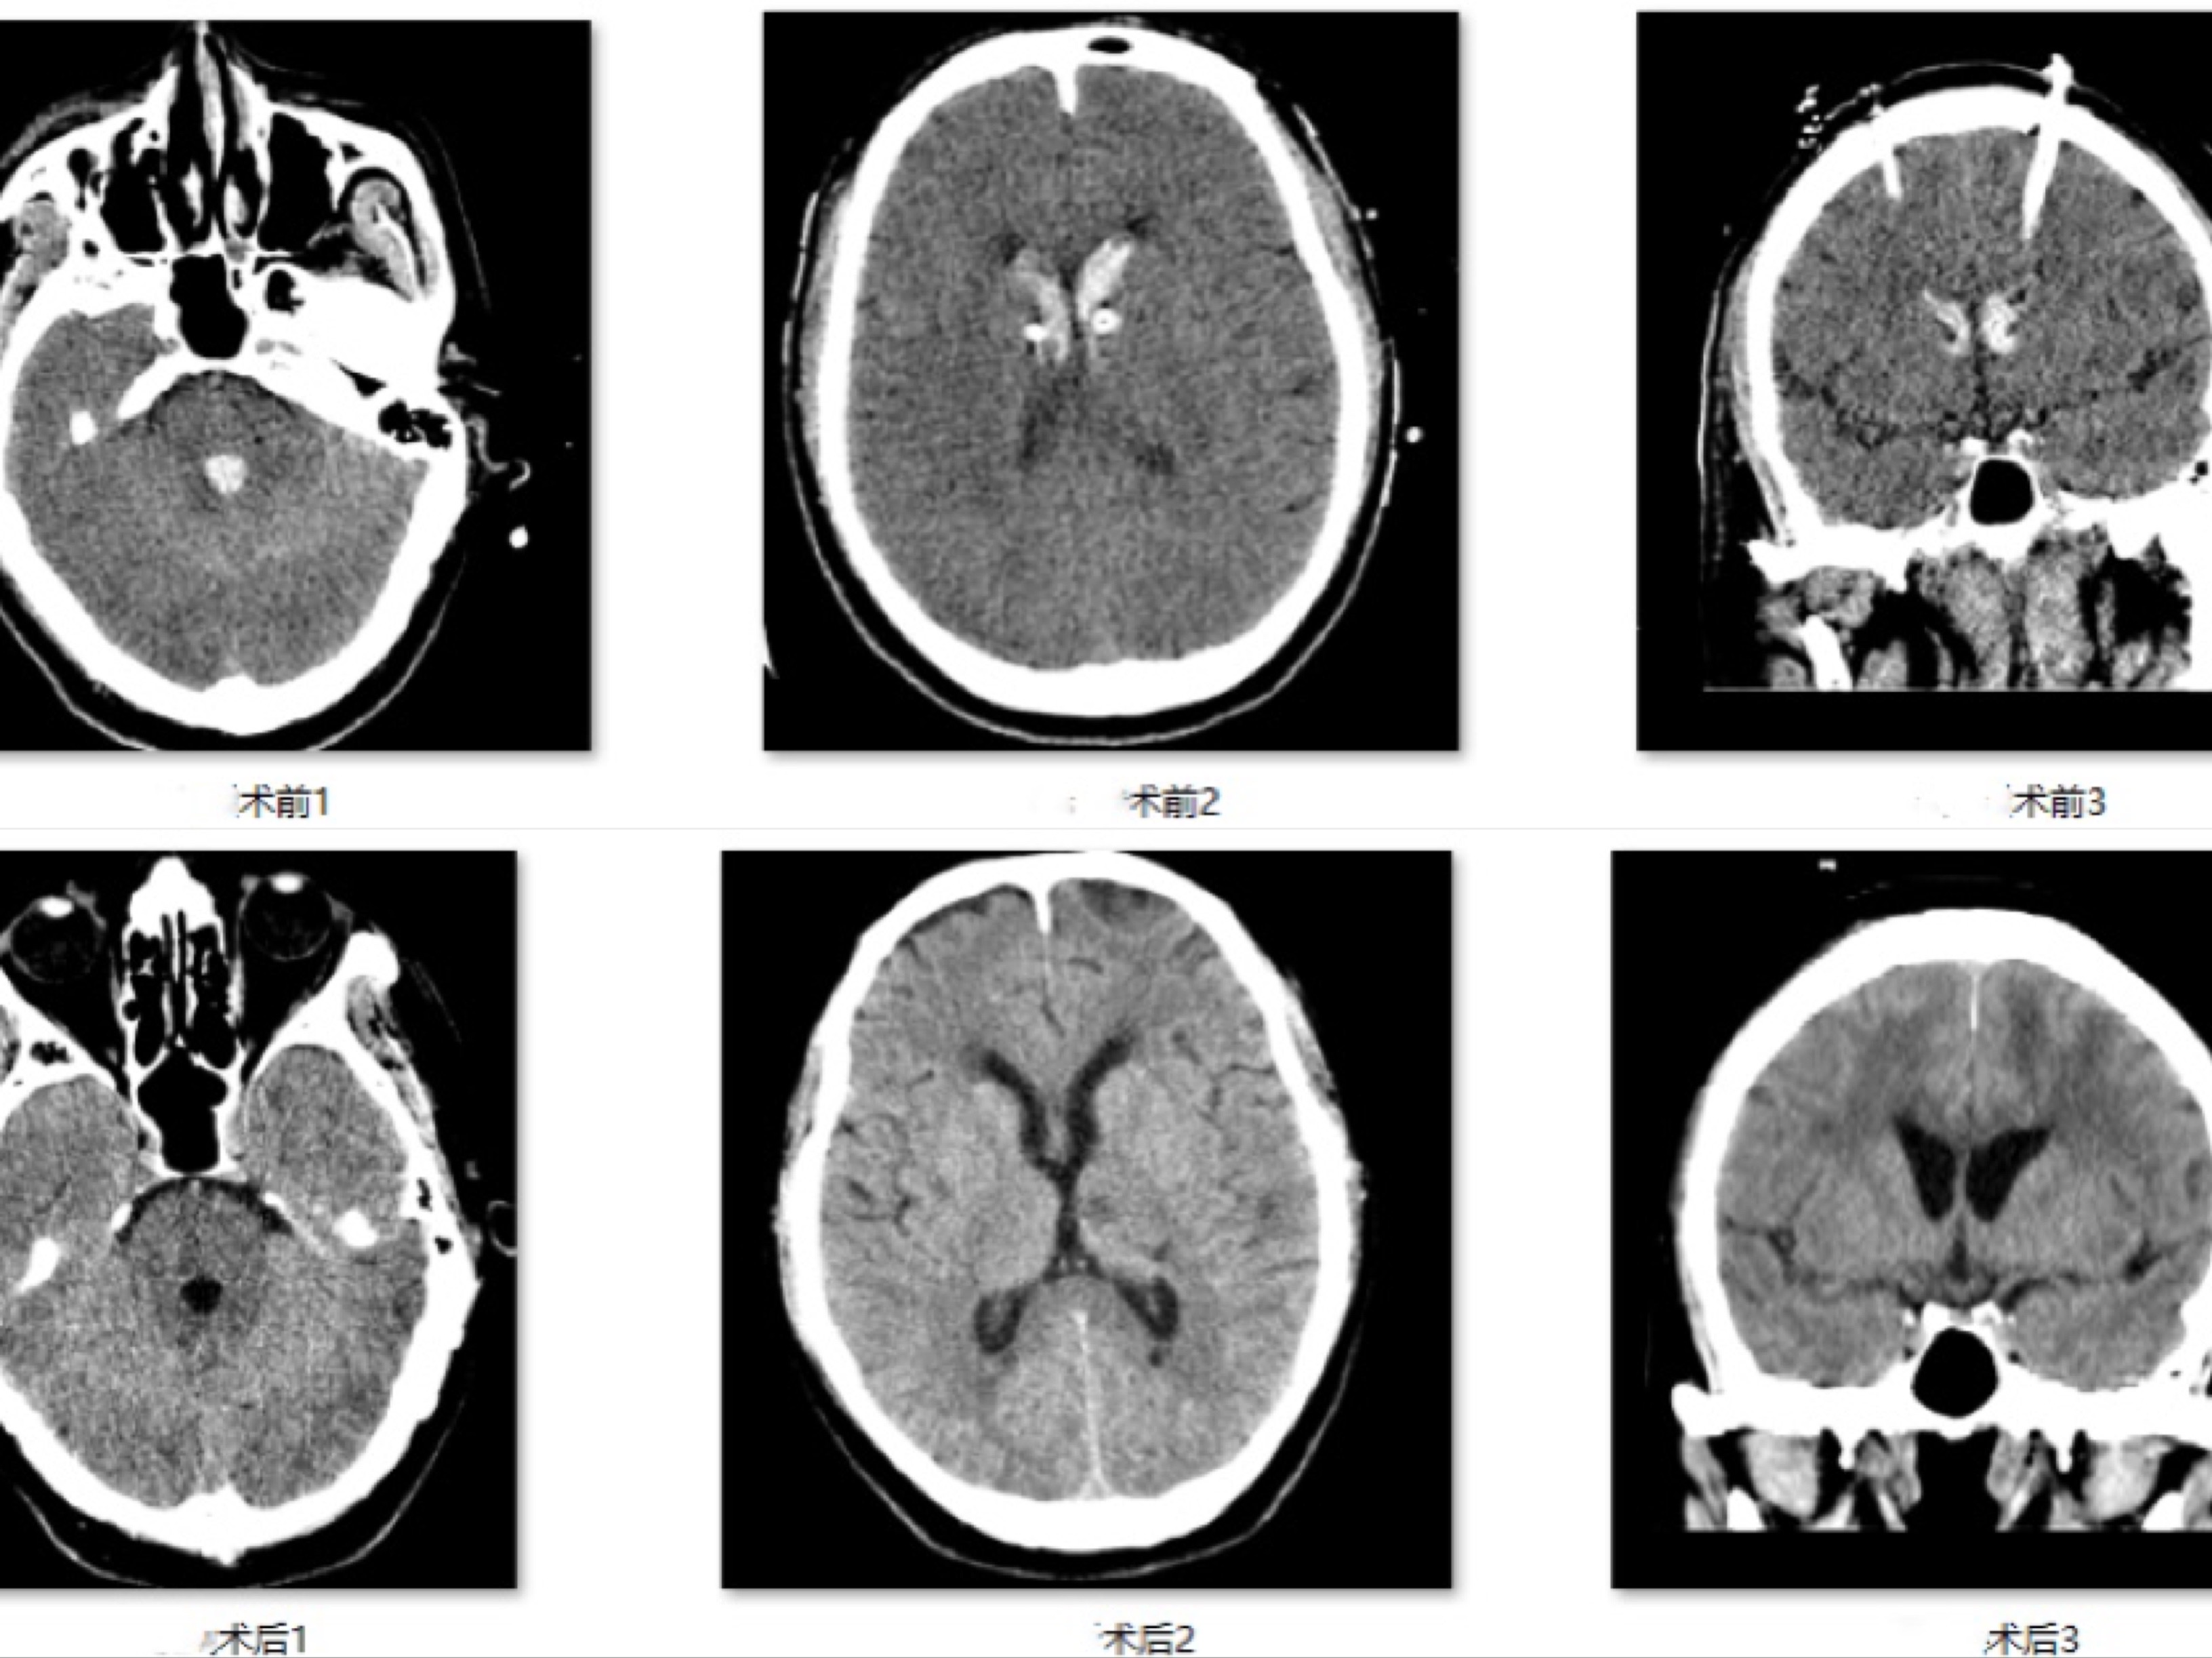

据主管医生回忆:2021-01-14老田家属联系我们时 , 左右脑室各有一根外引流管 , 患者嗜睡状态 , 言语混乱 , 精神弱 , 无法自主咳嗽 , 从片子上看考虑左侧基底节出血破入脑室 , 在双侧脑室、第三脑室及第四脑室内形成血肿铸形 。 这种情况下通过单独双侧脑室外引流清除血肿 , 一来血肿机化像果冻一样难以短期内通过液体引流的方式清除;二来这种胶状的血凝物很容易堵塞引流管;三延长引流时间又带来感染风险大大增加 。 与此同时 , 第三脑室、第四脑室内因残余积血难以彻底清除 , 对整体脑脊液循环的影响和周围组织的炎性刺激 , 远期并发脑积水和神经功能损伤的机会也会显著上升 。

入院后积极完善术前检查 , 拟行软性神经内镜下清除双侧脑室、第三脑室、第四脑室内的积血 , 保证导水管通畅 , 术中冲洗脑脊液清亮 , 并拔除原有的2根临时引流管 , 重新放置1根脑室腹壁外引流管 , 方便长期监测脑脊液情况 , 并安全规避了感染风险 。

手术进行的很顺利 , 患者术后自主呼吸、主动咳嗽能力可 , 经过评估拔除气管插管 。 经过2周的对症治疗 , 监测脑脊液化验未见明显异常 , 患者也可耐受关闭外引流 , 于2021-02-01拔除脑室腹壁外引流管 , 术后复查头颅CT除外出血 , 脑室形态未见增大 。 出院时 , 神志清 , 言语流利 , 记忆力逐渐恢复 , 可独立平稳行走 。